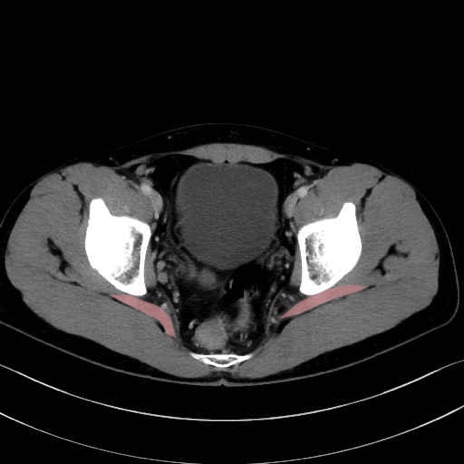

梨状筋 (Piriformis)